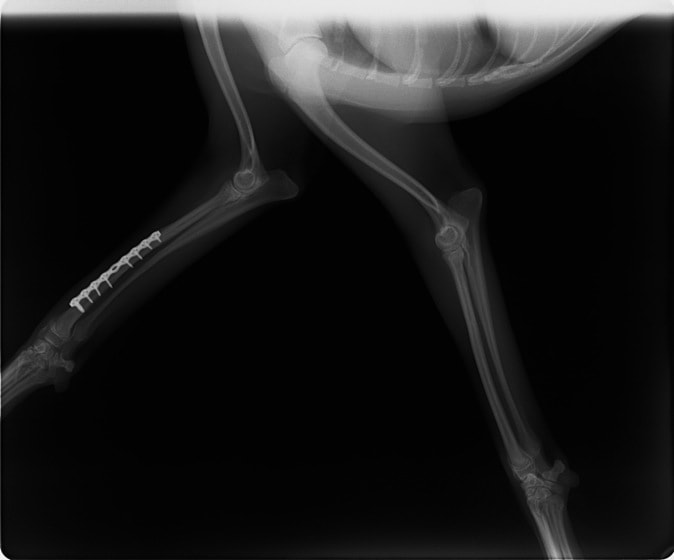

症例3:キルシュナーワイヤーのピンニングによる整復

ペルシャ猫 11ヶ月齢 雄

他院にて左大腿骨遠位の成長板骨折(salter-harrisⅠ型)が認められており、治療相談を目的として来院。当院にて、キルシュナーワイヤーを用いたピンニングにより骨折部位の整復を行いました。術後の経過は良好で、現在も経過観察中です。

術前レントゲン

術後レントゲン